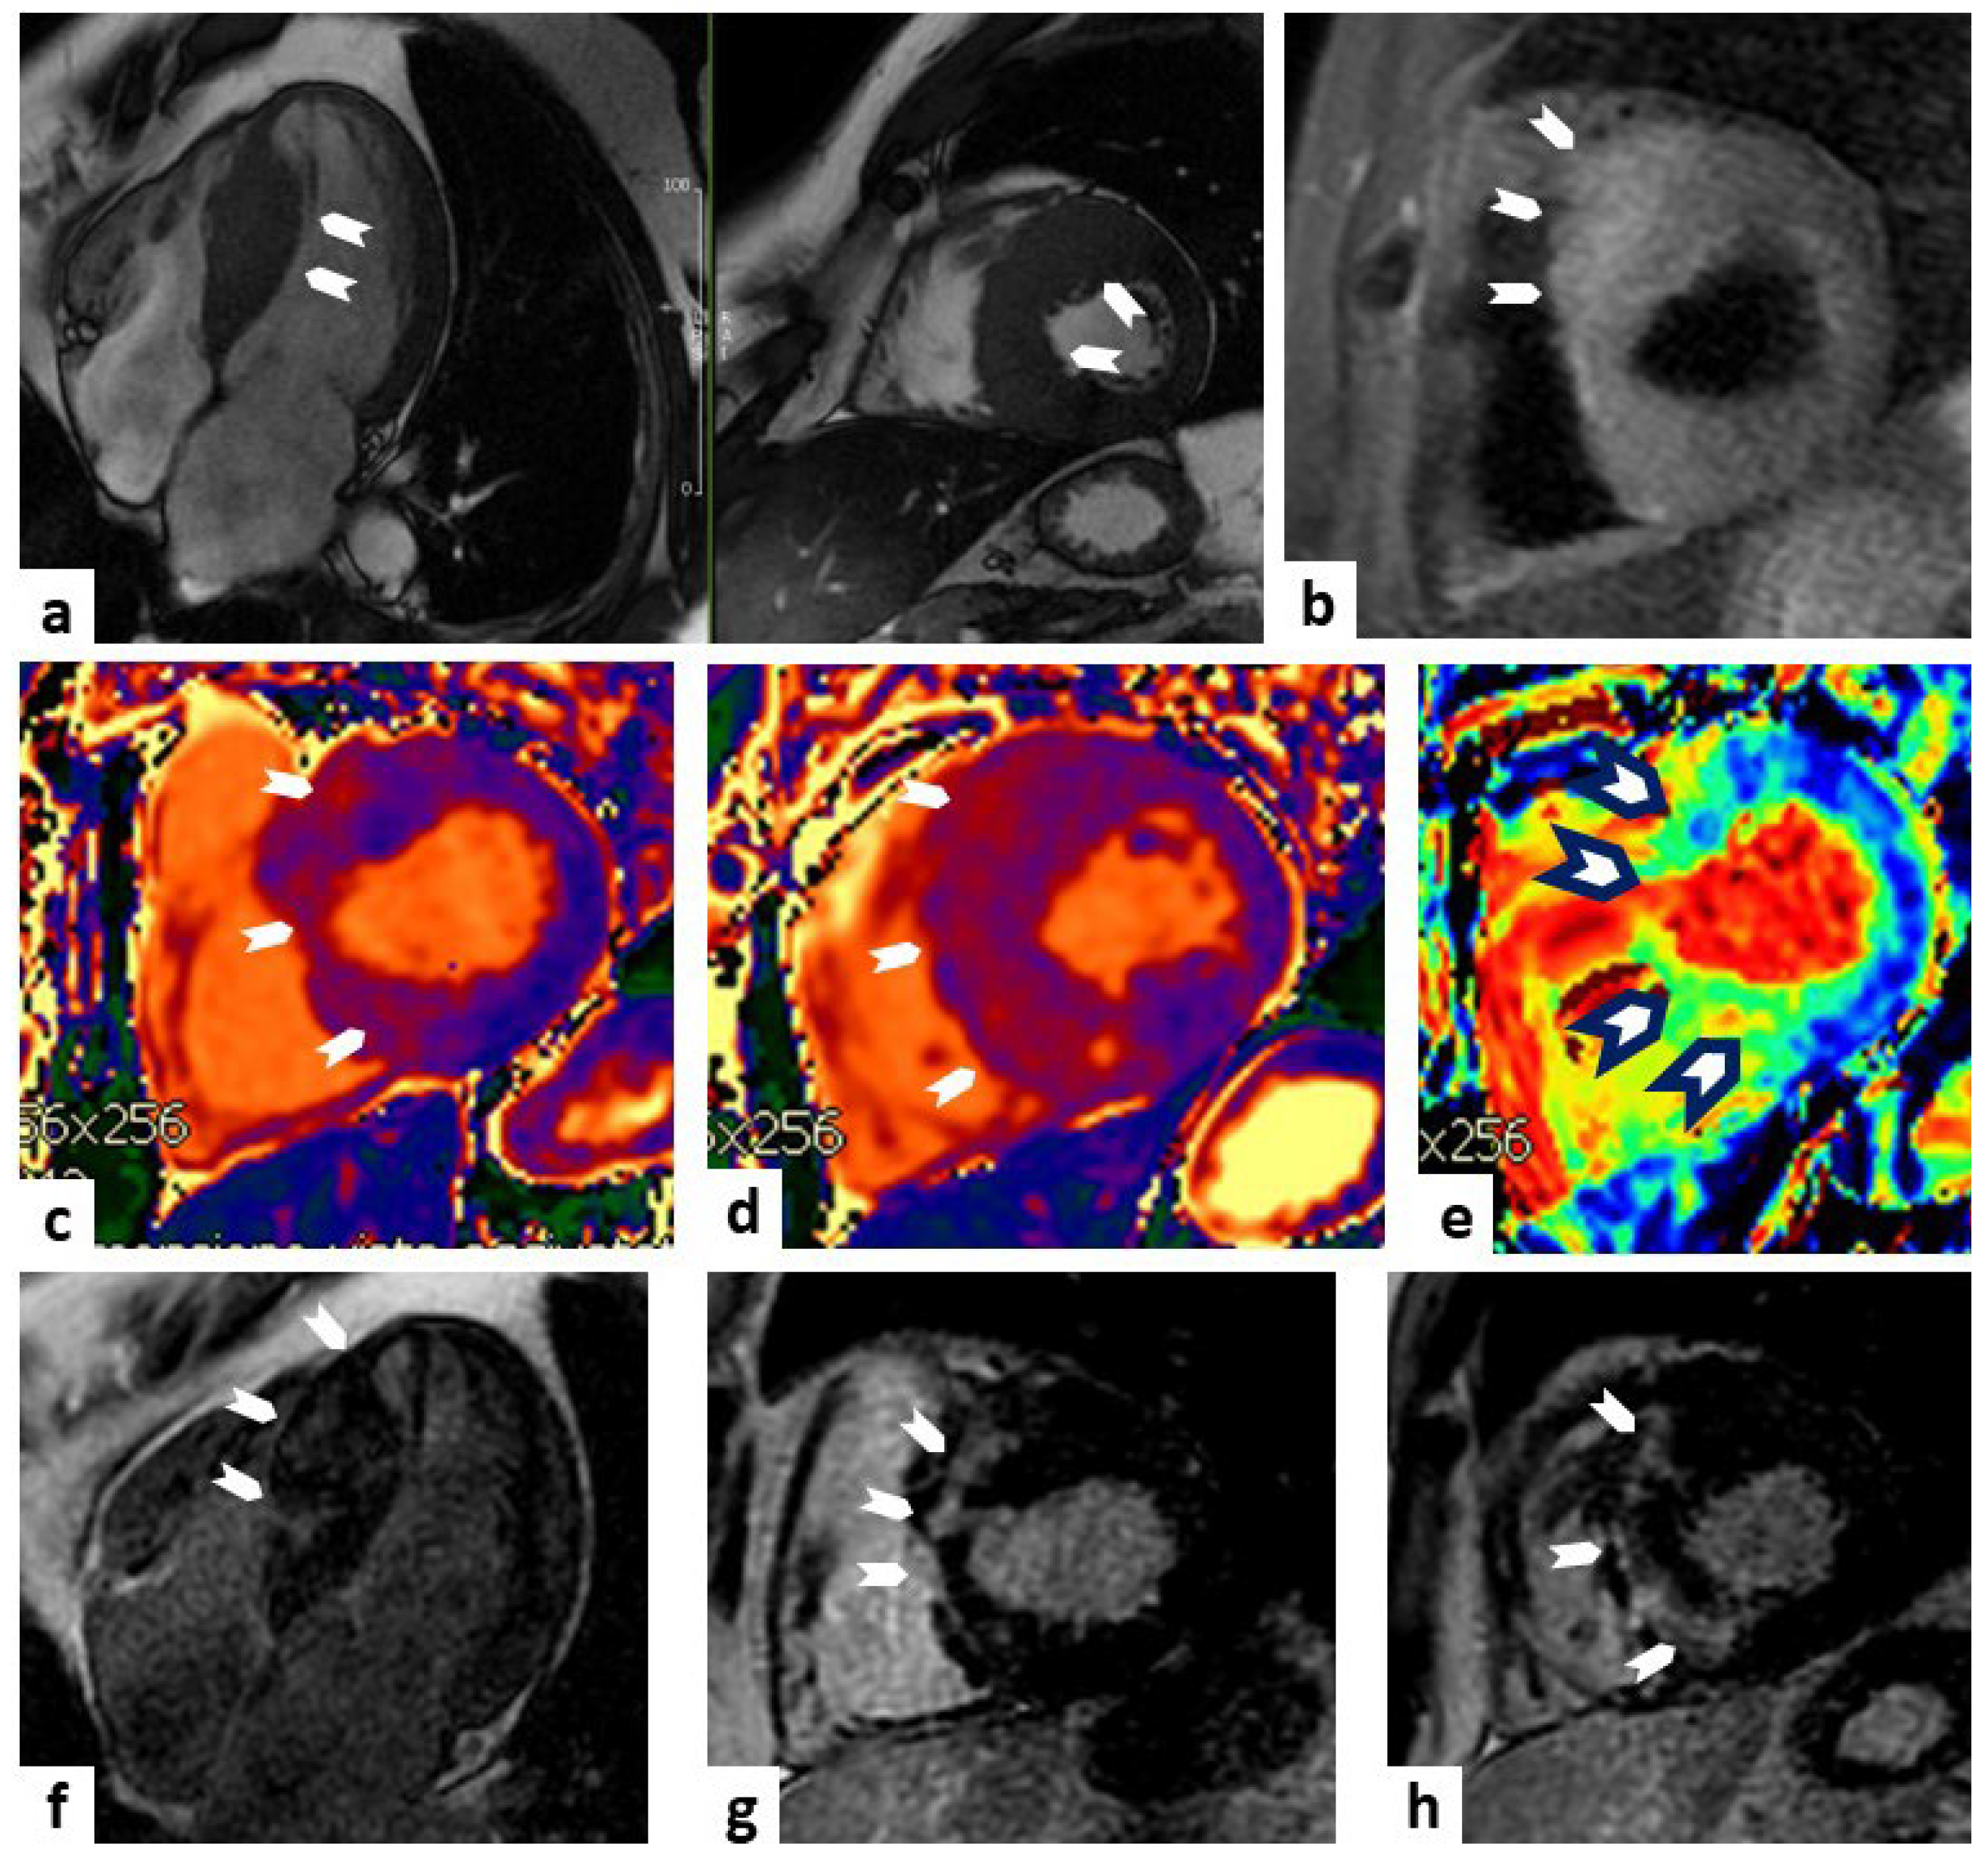

MRI is considered the gold standard in the differential diagnosis of different forms of cardiomyopathy with hypertrophic phenotype (Figure 1).

Figure 1.

Cardiac MRI of hypertrophic cardiomyopathy (HCM). A case of a 38-year-old male with a history of premature ventricular beats. Panel (a) (SSFP sequences) represents a four-chamber and short axis views (top left panel and top middle panel, respectively) showing a marked and asymmetric hypertrophy of the interventricular septum (white arrowheads). Panel (b) (TIR t2 sequence) represents a short-axis view showing a higher signal al the level of the septum (white arrowheads) compared to the remote myocardium. Panels (c,d) represent increased values on T1 mapping sequences at the level of the basal and middle septum (white arrowheads), respectively. Panel (e) represents increased values on extracellular volume (ECV) sequence at the level of middle septum (white arrowheads black outlines). Panels (f–h) (LGE sequences) display a non-ischemic pattern of hyperenhancement at the level of septum (white arrowheads). Taken together, these findings are diagnostic of asymmetric HCM.

T1 and T2 mapping helps identify areas of fibrosis, edema, and inflammation, aiding risk stratification and treatment planning. Quantitative cardiac MRI data contribute to a better understanding of disease progression and guide interventions, such as septal reduction therapies.